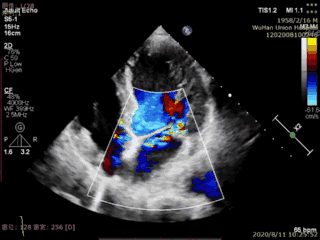

本例患者是一名高龄男性,合并多种疾病,术前超声心动图显示二尖瓣后叶P2脱垂、连枷伴重度二尖瓣反流。手术在食道超声引导下进行,植入1枚IIIs型二尖瓣夹合器,术后即刻显示二尖瓣反流消失,导管操作时间不到20分钟,手术取得圆满成功。

术前超声图